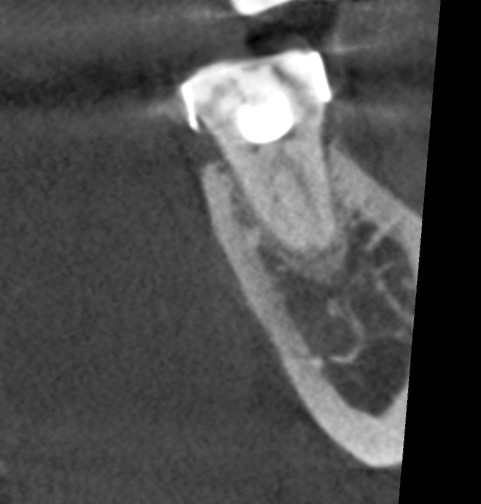

I investigated further with CBCT.

#37 mesial root coronal slice.

The coronal slice of the mesial root clearly showed the singular mesial canal dividing into two in the coronal 1/3.